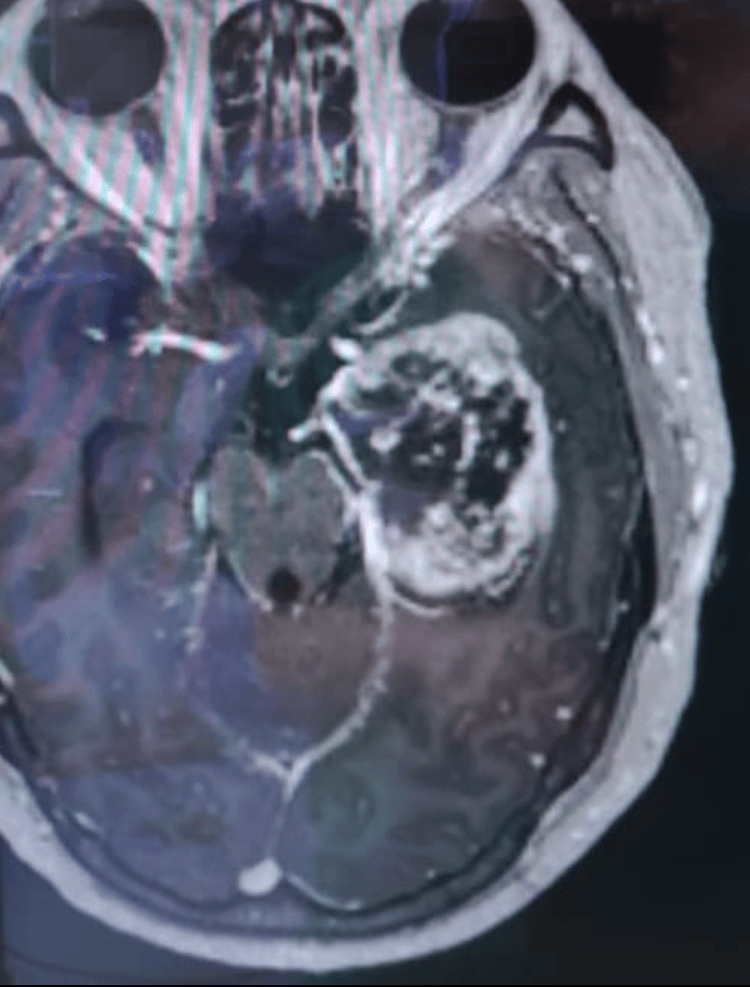

I'm Dr. David Wasilewski, a senior neurosurgery resident (PGY-6) at University Hospital Düsseldorf, with prior training at Charité – Universitätsmedizin Berlin and a research fellowship at CNIO Madrid. My clinical and scientific focus lies in glioblastoma, lower-grade gliomas, brain metastases, and general neurosurgery. I’ve contributed to multiple peer-reviewed publications (H-index 9), co-supervised doctoral theses, and led or co-led translational research projects in neuro-oncology across Europe. Furthermore I am interested in patient education and conveying information from the neurooncology community to a broader public. This site shares selected educational resources for patients/relatives and also doctors in terms of specific topics in neurooncology and neurooncology practice.